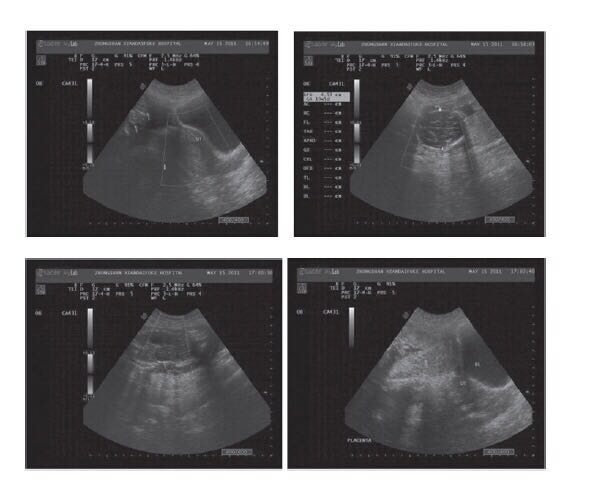

女,22岁,停经4个多月,在其他医院做了药流失败,前两天又做羊膜腔内注射:利凡诺100mg,引产失败。病人腹痛来我院就诊,病人痛苦面容。 腹部彩超:子宫前位,大小约:65*43*58mm,形态正常,轮廓清晰,实质回事均匀,子宫内膜厚约:10mm,清晰居中,未见明显占位性病变。 双侧卵巢显示不清。CDFI:未见明显异常血流。 腹腔内可见一胎儿回声,胎头位于右上方,颅骨环完整,双顶径约:46mm,股骨长约:34mm,脊柱连续。未探及胎心榑动及胎动,胎心率:0次/分。四肢因胎儿遮挡显示不清,颜面部显示不清,胎盘位于子宫上方,腹腔左侧I级,羊水深:32mm。腹壁与胎头之间厚约:7mm,未见子宫实质回声,未探及宫颈回声与另一子宫没有关系。矢状切面图,可见妊娠囊位于子宫(ut)的上方。内有胎儿。矢状切面图更清晰地显示子宫轮廓,明确妊娠囊位于子宫上方,并与子宫分隔开。 诊断?